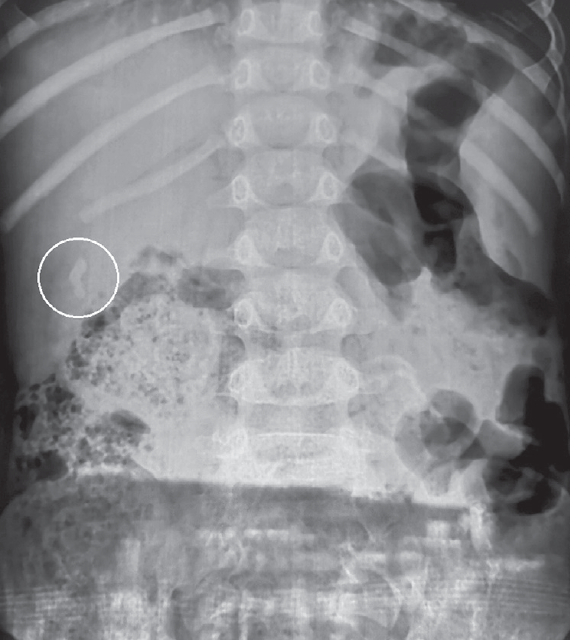

После установления диагноза ЖКБ всем пациентам проводилась обзорная рентгенография брюшной полости с целью обнаружения кальцинированных конкрементов в желчном пузыре. У двух пациентов они были четко визуализированы, вследствие чего детям консервативное лечение не проводилось и были установлены показания к оперативному лечению (рис. 3).

Рис. 3. Кальцинированный конкремент в желчном пузыре

Fig. 3. Calcified brupor in the gallbladder